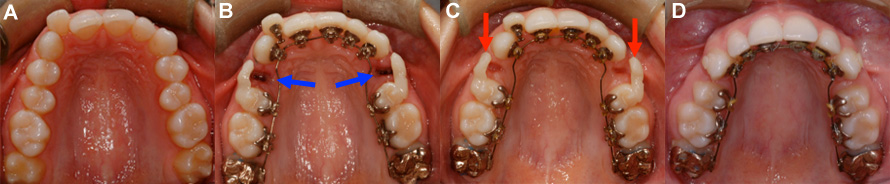

Solutions esthétiques pour dents manquantes pendant l’orthodontie-3

Rétraction de dents antérieures à l’aide de broches linguales iBraces. (A) Condition initiale avec dents antérieures avancées et chevauchées. (B) Une prémolaire a été extraite de chaque côté (flèches bleues) afin de donner l’espace nécessaire pour reculer les dents antérieures. (C) Facettes collées sur les prémolaires (flèches rouges) pour camoufler l’espace d’extraction pendant la rétraction. (D) Après quelques mois, les dents sont partiellement reculées, l’espace d’extraction a diminué et les facettes peuvent être enlevées. Ce cas en cours de traitement n’était pas terminé lors du montage photographique.